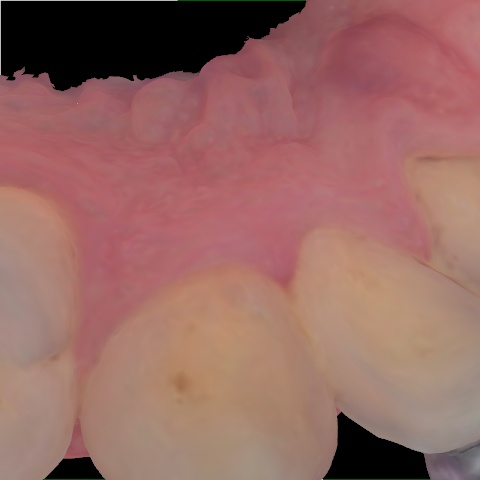

Image 1506 / 2000

NHD39969

Annotated as "Good"

Original Image Rendering Image